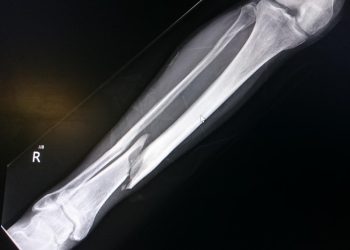

شکستگی استخوان پا یکی از شایعترین آسیبهایی است که هر فرد در زندگی روزانه خود ممکن است متحمل شود. از...